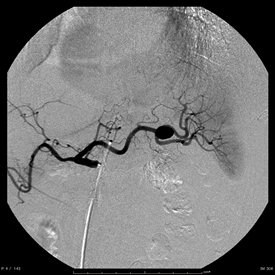

内臓動脈瘤への経皮的塞栓術

脾門部の動脈瘤に対して塞栓用コイルにて塞栓術を施行しています。